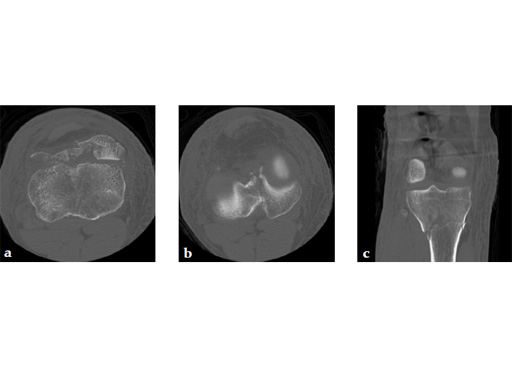

A 36-year-old man sustained a motorcycle injury: right femoral shaft fracture and right hyperextension bicondylar tibial plateau variant (Fig 1, Fig 2).

Staged management with initial rodding of femur and placement of spanning knee external fixator with closed manipulative reduction of tibial plateau (Fig 3).